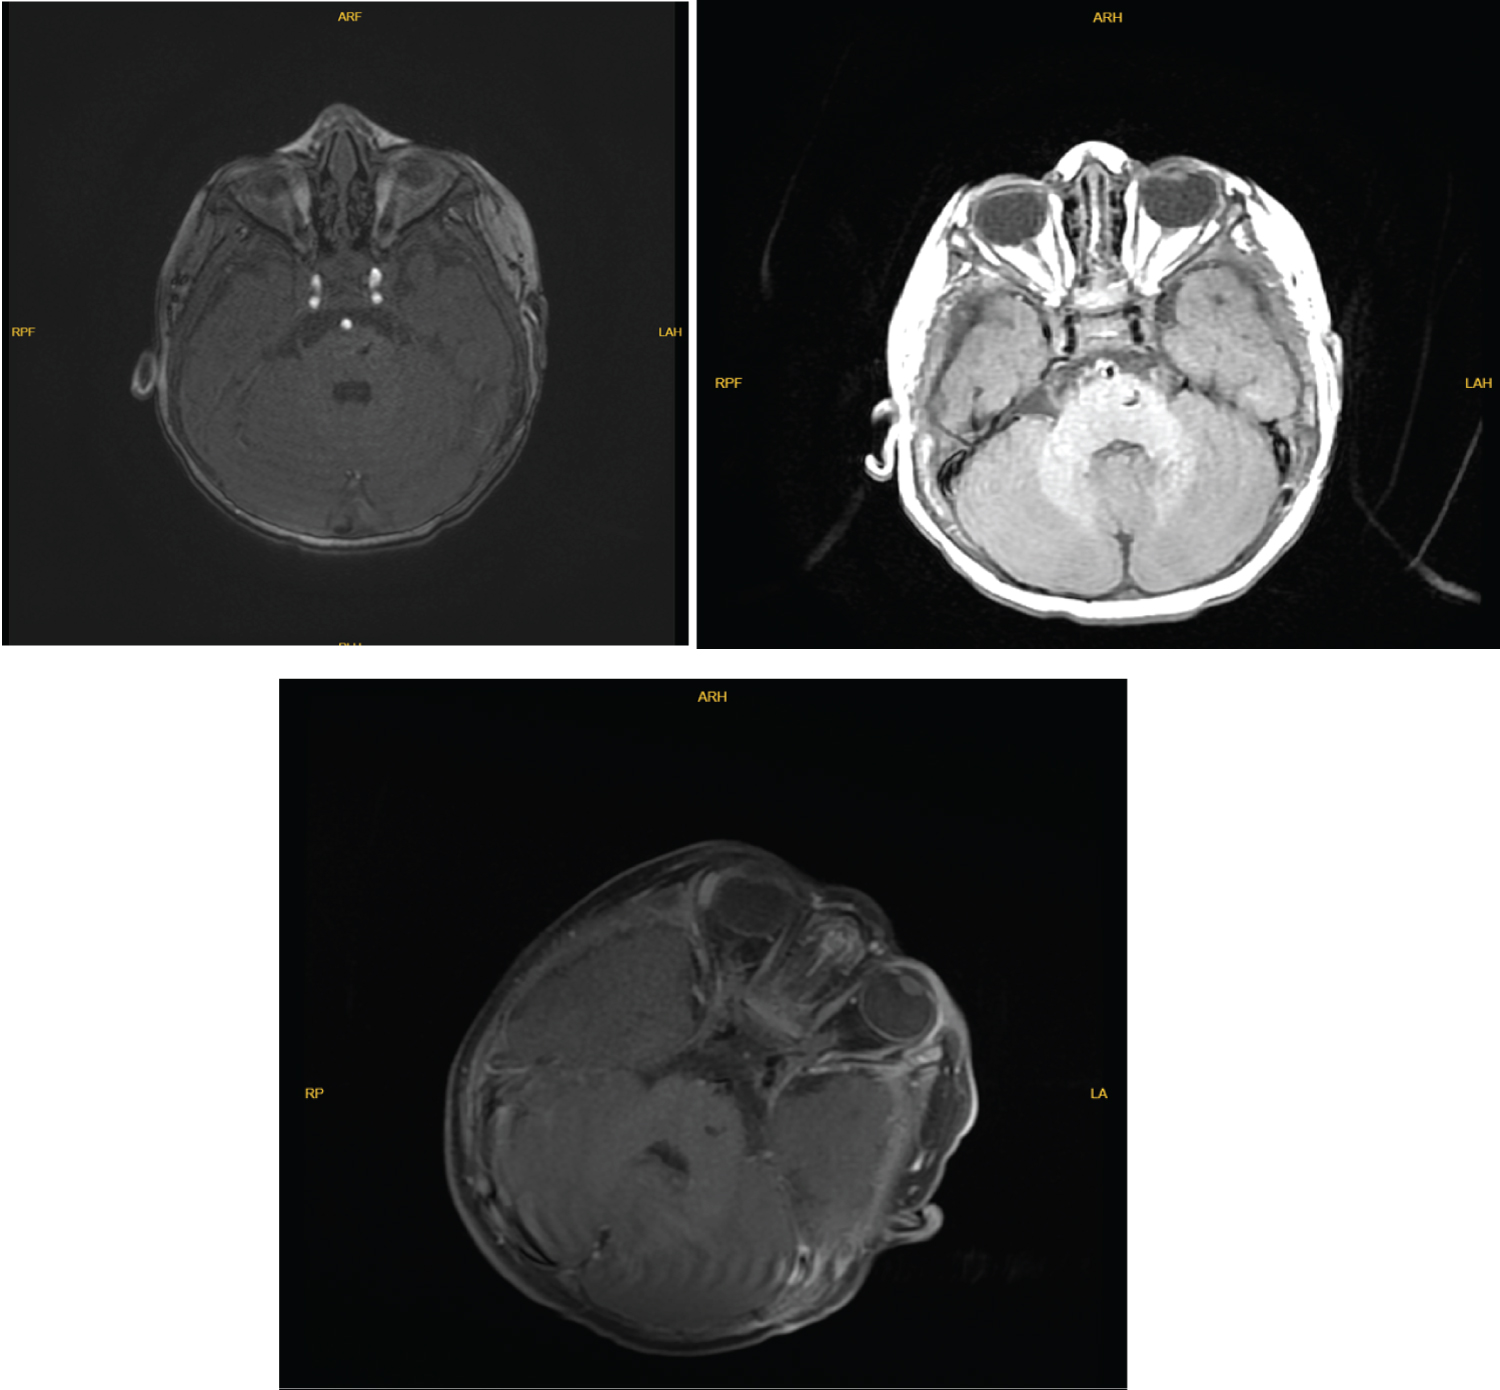

Blood tests were evaluated, and no pathologic value was seen. Magnetic resonance imaging (MRI) and angiography (MRA) was obtained which revealed a pontin mass along the dorsal aspect of the posterior fossa. The lesion is heterogeneously hyperintense on T1 and T2 weighted sequences (Figure 1 and Figure 2). The mass was well-circumscribed and heterogeneous, and evidence of previous hemorrhage within it. He was consulted to our department with preliminary diagnosis of pontine cavernoma and hemangioma. The differential diagnoses of an intracranial vascular lesion in this one year-day old infant included hemangioma, hemangioblastoma, vascular malformation, and other neonatal tumor types, such as soft-tissue sarcoma [8].

Figure 1: MR angiography showed a non-vascular lesion narrowing forth ventricle on the left part of pons. View Figure 1